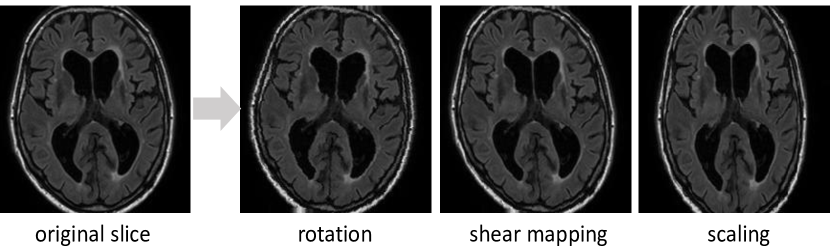

3.1.1 Data augmentation

Data augmentation is an effective way to equip the deep networks with desired invariance and robustness properties when training data are limited. In case of MR images among different subjects and scanners, due to variations of head orientations, voxel sizes and WMH distribution, we primarily need rotation and scale invariance as well as robustness to shear transformation. For each axial slice, three transformations including rotation, shear mapping and scaling were applied, each within a parameter range. The parameter range represents the variation in different aspects between subjects in clinical practice; for example, rotation of brain is in the range of [-15°, 15°]. Table 2 lists the parameter range for each of the three transformations. It should be noted that the scaling used in the training of the algorithm was in the range of (0.9, 1.1), representing the range of voxel size ratios in the training data sets (Table 1), while some test sets had noticeable larger ratios (a factor of 1.21 between the PETMR and the Singapore data set). This indicates the robustness of our approach, but also leaves potential room for improvement in future studies exploring the optimal scaling of the data during training.

Figure 3 shows an example of the resulting slices after applying the transformations. After data augmentation, we obtain a dataset ten times larger than the original one.